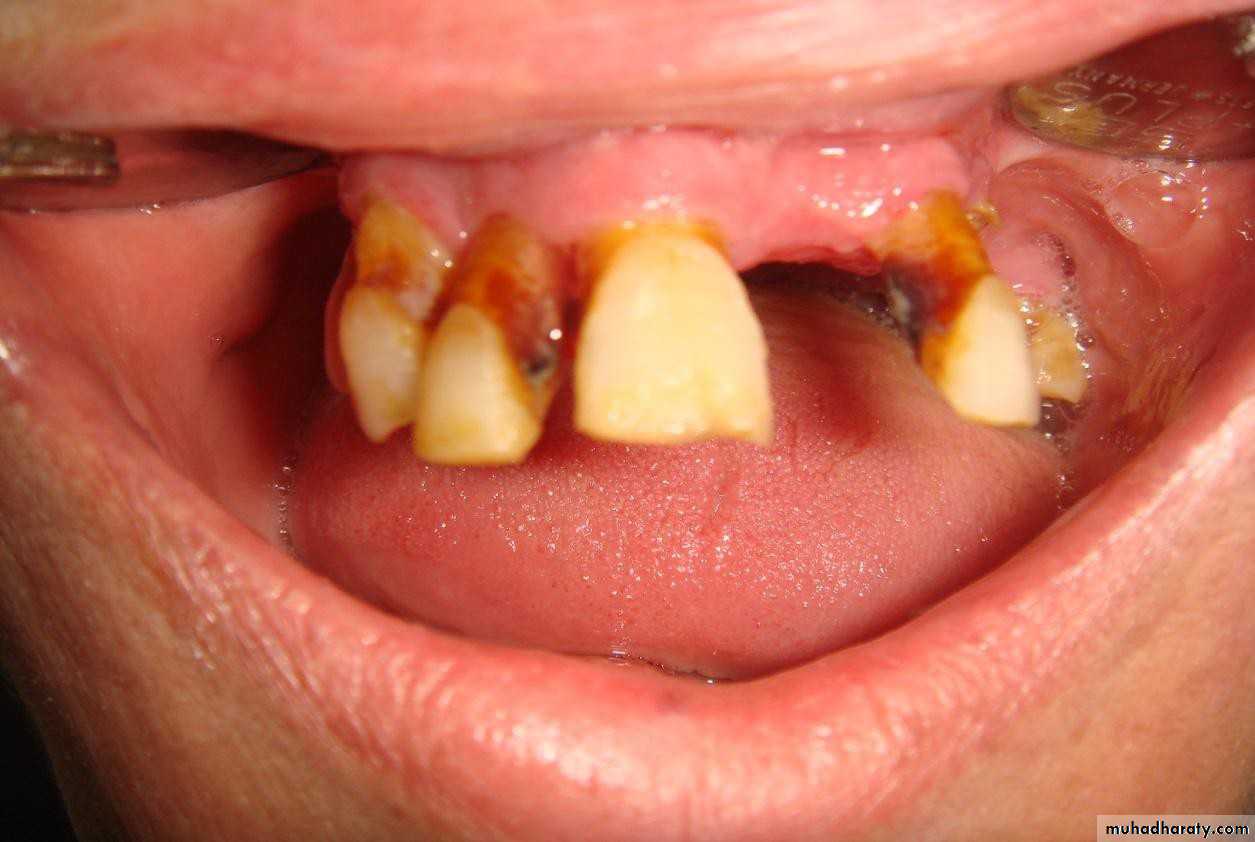

• 1) Few remaining teeth or teeth with an unfavourable distribution in the arch which precludes treatment with a removable P.D.

• 2) Severe loss of periodontal attachment in a patient who cannot afford a fixed partial denture

• 3) Complicated functional and aesthetic conditions due to tooth migration which make restoration with a removable or fixed partial denture difficult.

• 4) Significant tooth loss due to attrition.